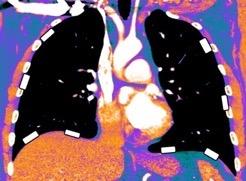

Tromboembolismo pulmonar.

Frecuencia del derrame:

Rx: 32%. TC: 47%

Unilateral. 85%

< 1/3 del hemitórax: 90%

Todos exudados

58% con eritrocitos

21% tabicación lo que causa demora en el diagnóstico

TEP. Empiema pleural. Atelectasia redonda

Porcel JM et al. Analysis of pleural effusions in acute pulmonary embolism: radiological and pleural fluid data from 230 patients. Respirology 2007/ Iguchi T et al. Desquamation of the subpleural lung parenchyma caused by empyema after pulmonary embolism: A case report. Respirol Case Rep. 2022 .

Derrame pleural 43-48% de pacientes con embolismo.

< 1/3 de hemitórax: 90%.(puede haber en lado opuesto).

Siempre exudados.

75% de los pacientes con TEP y derrame pleural tienen dolor pleurítico.

La disnea desproporcionada